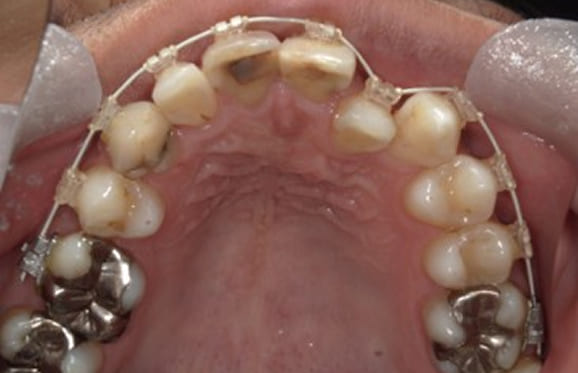

● C4を超え歯根までの虫歯を抜歯、スペースを利用して歯並び全体を整えた症例

藤沢デンタルオフィスの虫歯や破折で抜歯後の部分矯正